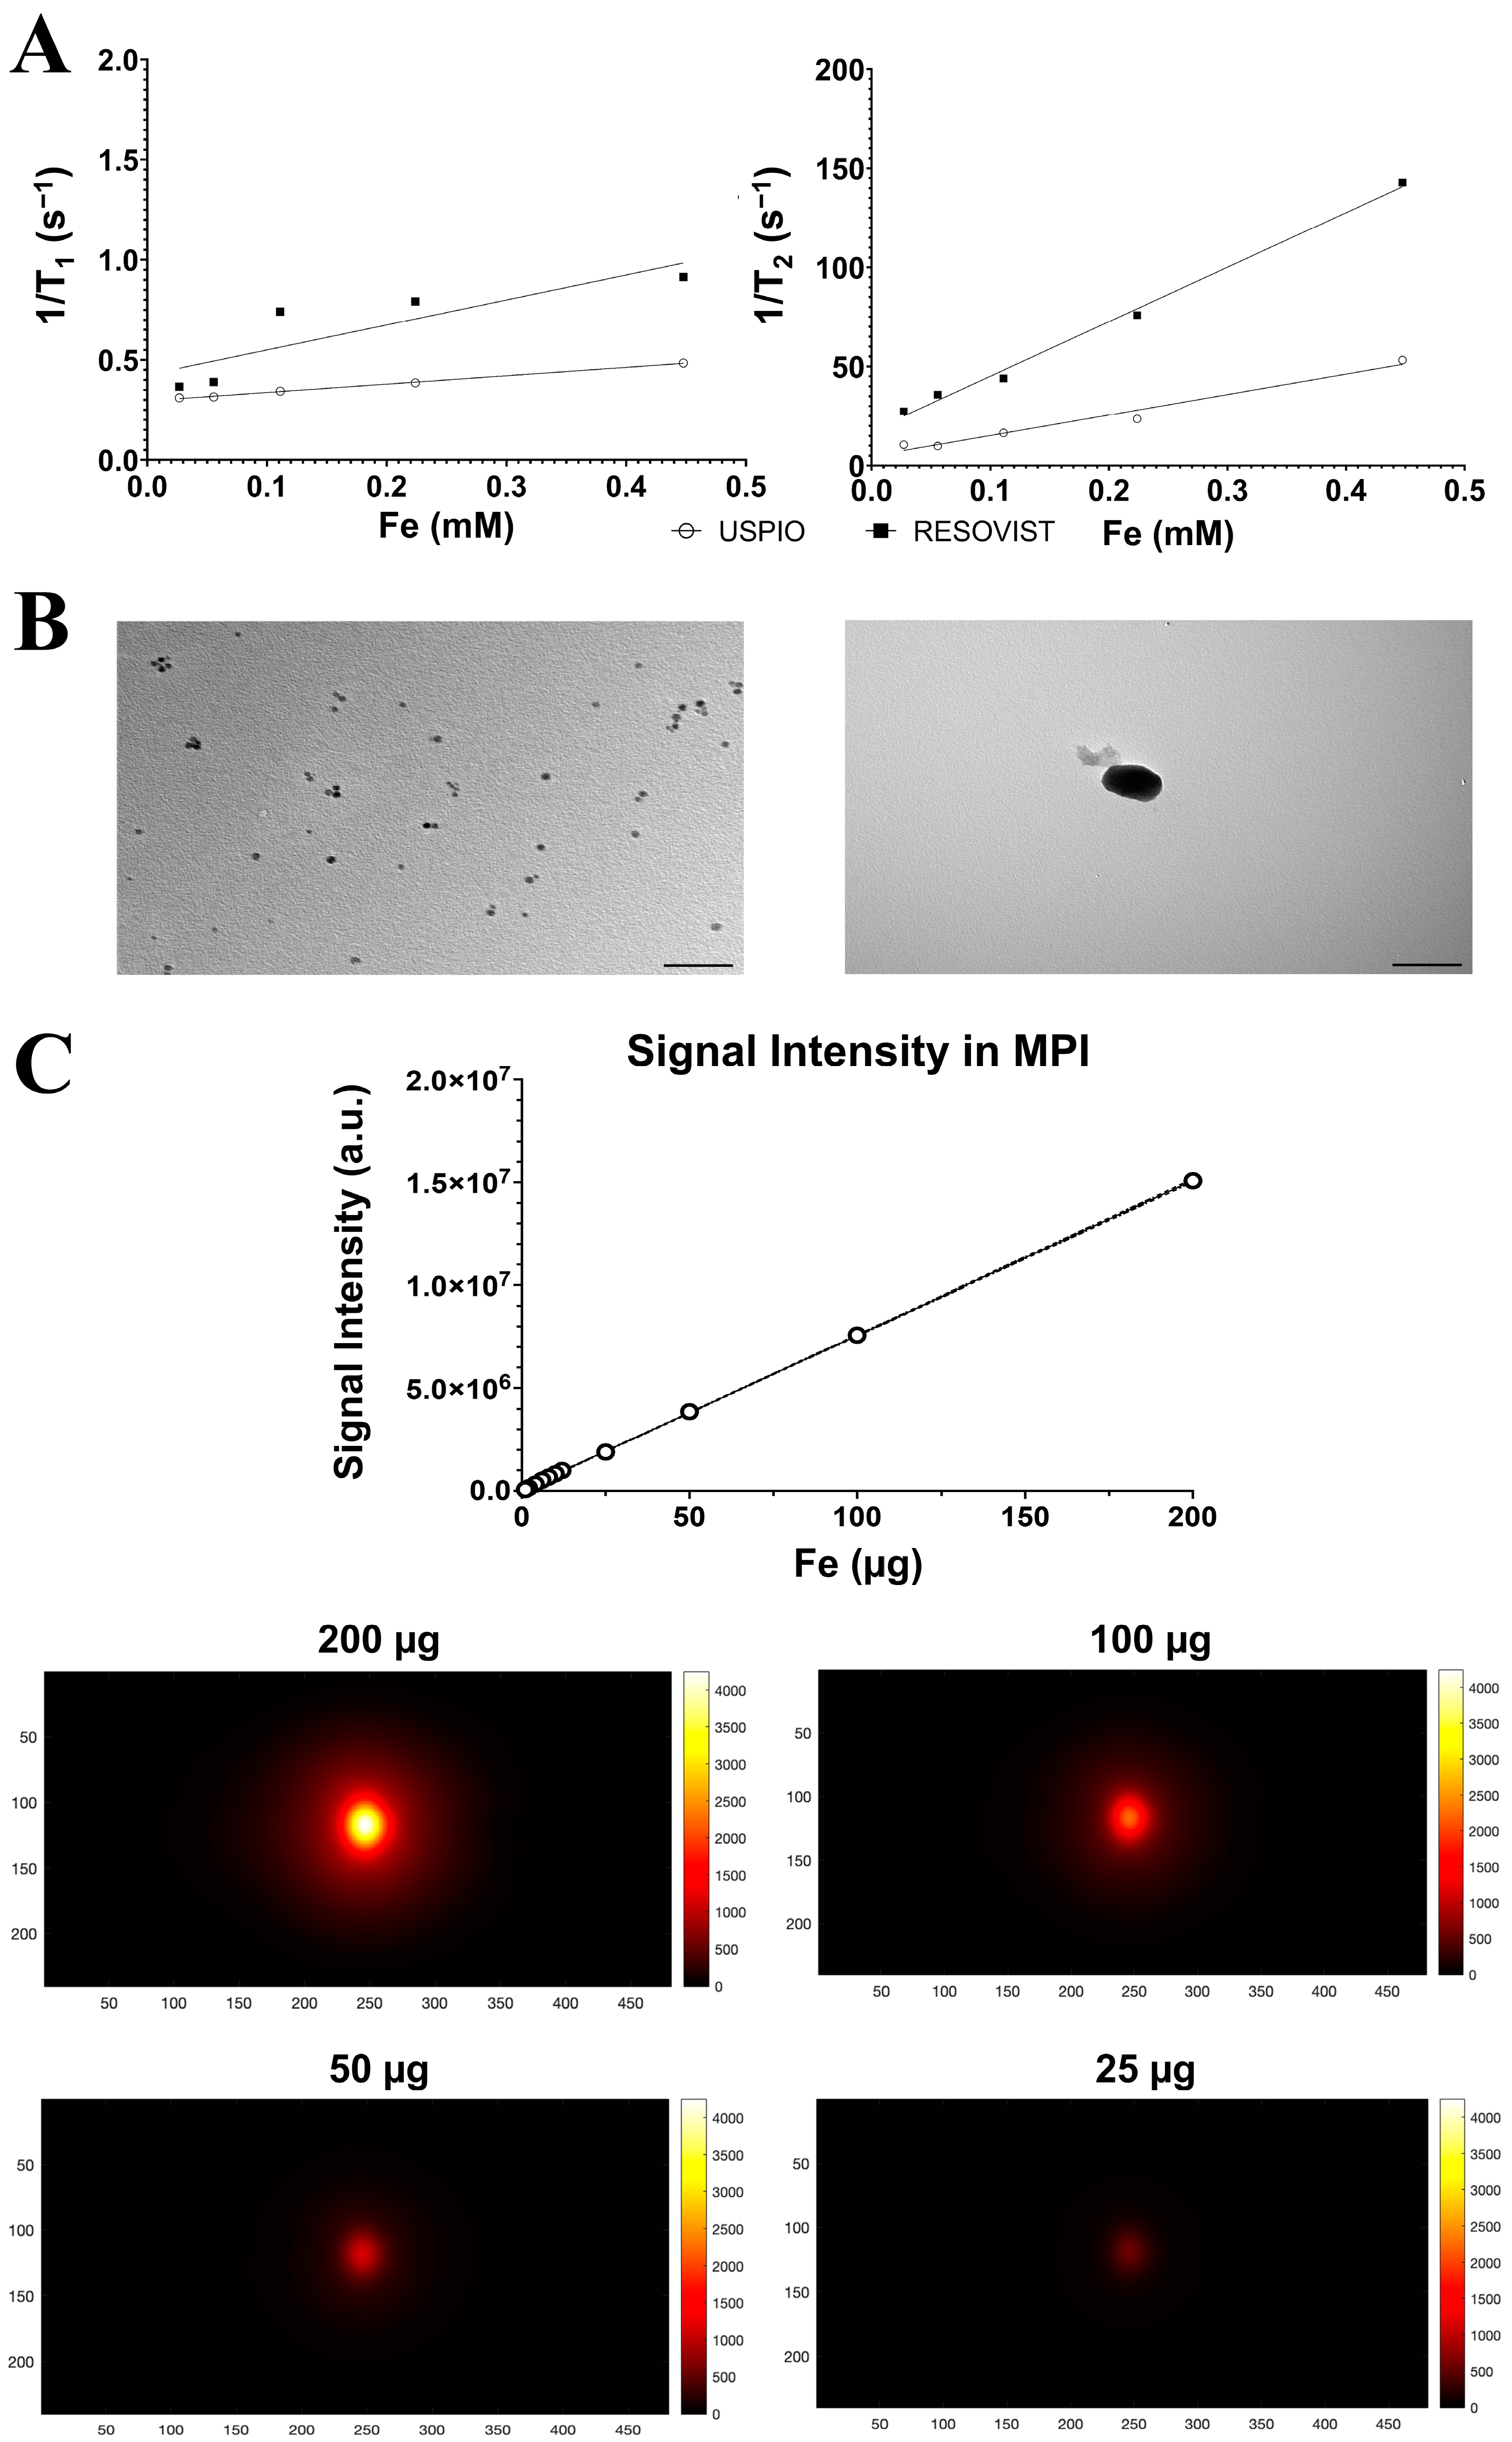

2.1. Nanoparticle Characterization

4.1. Physical–Chemical Characterization of Nanoparticles

| USPIO in Distilled Water | USPIO in Agar Gel 2% | Resovist® in Distilled Water | Resovist® in Agar Gel 2% | |

|---|---|---|---|---|

| Size on Light Scattering (Size Peak nm ± SDev) | 9.5 ± 2.01 | 69.18 ± 1.56 | ||

| Zeta Potential (mV ± ZDev) | −23.6 ± 1.7 | −31.8 ± 7.12 | ||

| Size on Transmission Electron Microscopy (nm ± SDev) | 5.0± 0.01 | 70 ± 0.2 | ||

| Transverse relaxivity (mM−1 s−1) | Not measured * | 103.3 ± 2.122 | 176.6 ± 1.868 | 274.9 ± 4.108 |

| Longitudinal relaxivity (mM−1 s−1) | Not measured * | 0.4174 ± 0.018 | 1.736 ± 0.042 | 1.072 ± 0.07 |

| Ratio r2/r1 | 247.484 | 101.73 | 256.436 |